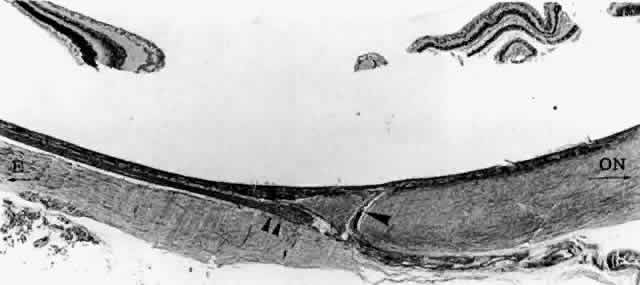

Fig. 18. Emissary canal in sclera for the long temporal posterior ciliary artery

and nerve (LTPCA and LTPCN). Submacular arterial branch (arrowhead) curves posteriorly to enter choroid abruptly. LTPCN (double arrowhead) and LTPCA slip into suprachoroidal space obliquely. Equator (E) toward left, and optic nerve (ON) toward right.(H & E, × 31) Fig. 18. Emissary canal in sclera for the long temporal posterior ciliary artery

and nerve (LTPCA and LTPCN). Submacular arterial branch (arrowhead) curves posteriorly to enter choroid abruptly. LTPCN (double arrowhead) and LTPCA slip into suprachoroidal space obliquely. Equator (E) toward left, and optic nerve (ON) toward right.(H & E, × 31)